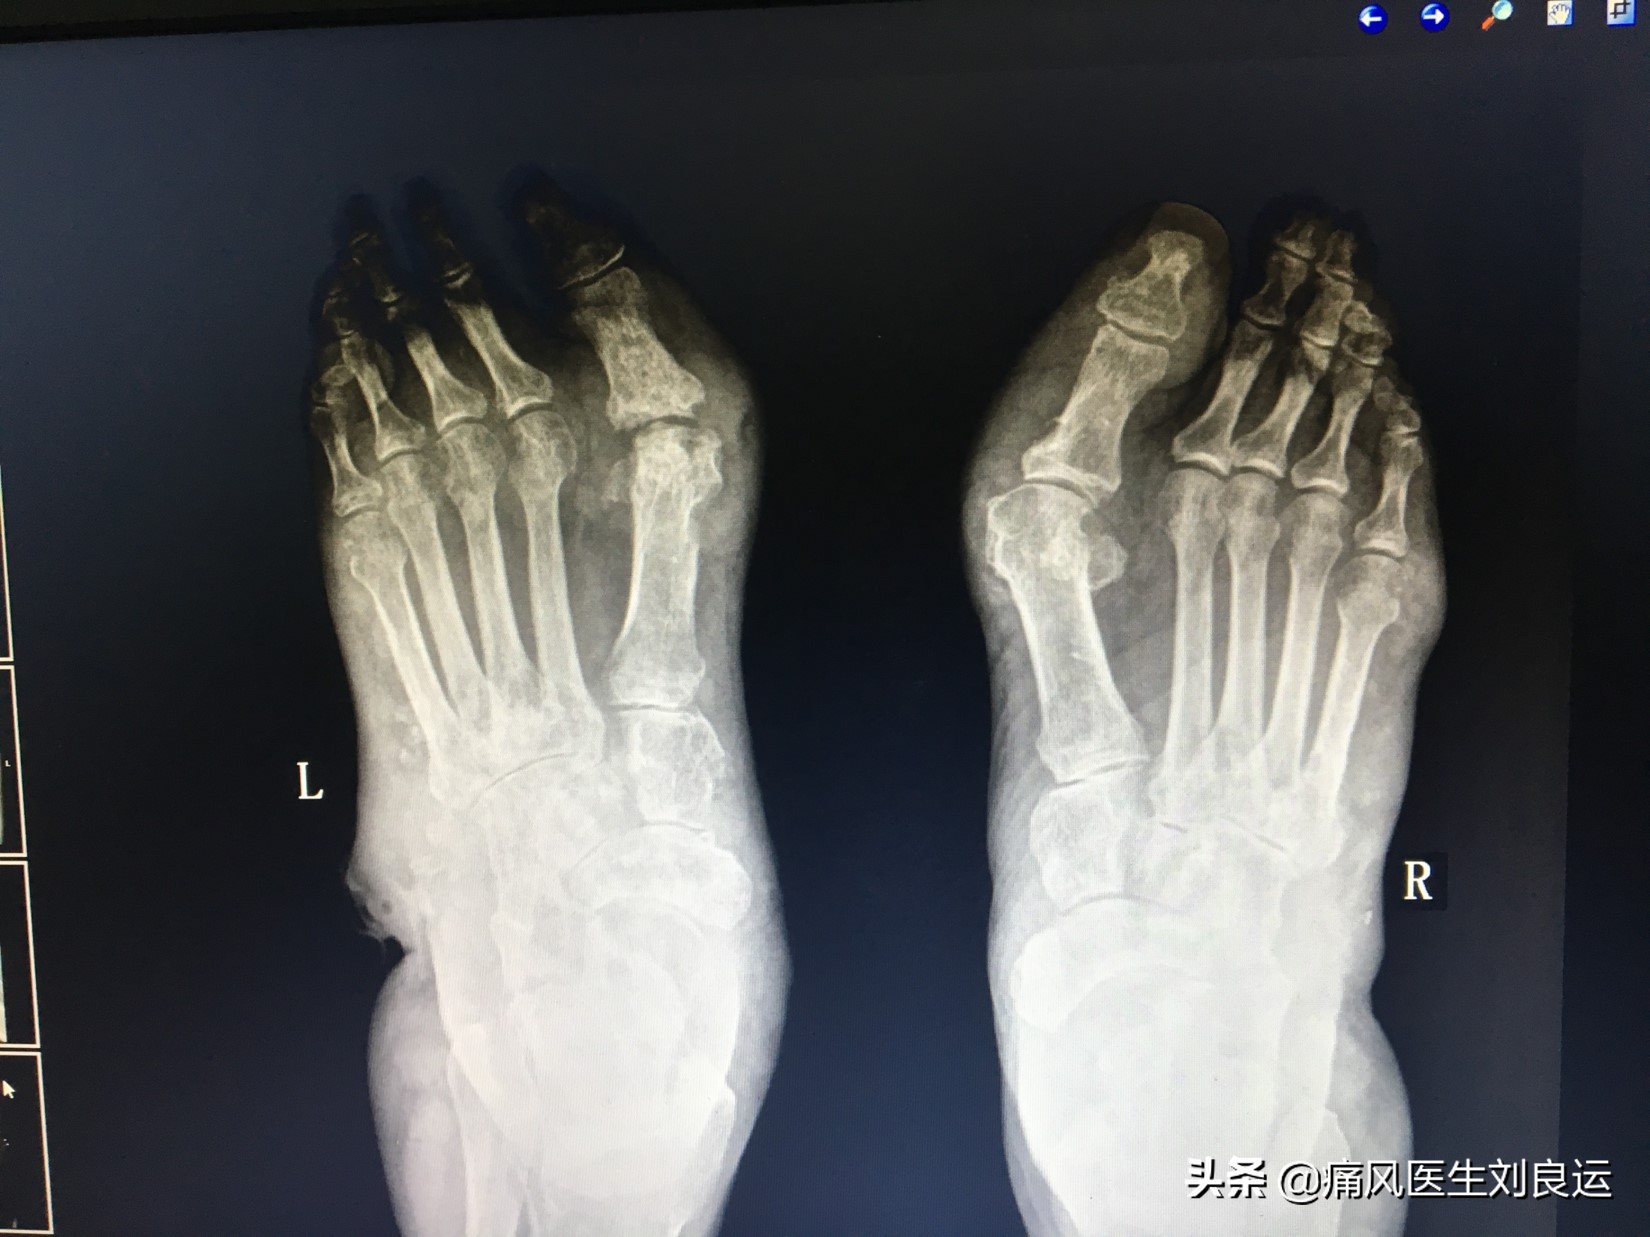

X线下双足痛风石

痛风石可见于任何关节软骨(透明软骨或纤维软骨)、滑膜、触鞘及其周围软组织;好发于外耳的耳轮、尺骨鹰嘴、指间和掌指关节、指端皮肤、手掌、腕关节、跖趾、踝关节、足背、足底、膝关节等处;少数病人可出现在鼻软骨、舌、声带、眼睑、主动脉、心瓣膜和心肌;大动脉、心肌、主动脉瓣、二尖瓣、三尖瓣、舌、会厌、也会出现痛风石;躯干部,如肩、胸、腹、背、腰、臀等处少见,大腿及上臂等处少见;可在关节附近的滑囊膜、腱鞘与软骨内发现。内压增高,常常会使局部皮肤膨胀、紧张、菲薄、发亮。加上尿酸盐结晶的侵蚀作用,覆盖其上的皮肤完整性受到破坏,抗牵拉性下降,一旦因摩擦、受压、受冻以及创伤等原因可发生溃烂,“牙膏样”白色尿酸盐结晶物质就会从破溃的洞里“漏出来。